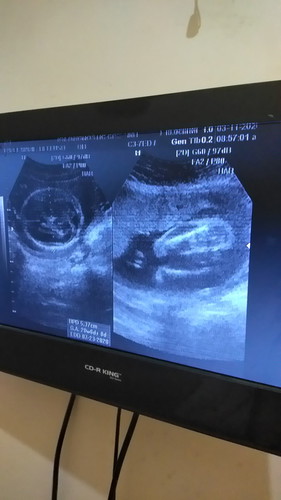

Baby girl

Sino same ng ultrasound ko mommies? ☺ baby girl daw po sabi ng sonologist 22weeks ako now. Naguluhan kasi ako dun sa neighbor ko baby girl din daw sakanya nung una tas pinabalik sya 7-8mos. lalake na nakita. Pagkalabas ng baby lalake nga ? possible pa ba magkamali sa 22weeks gender? Thank you!

Same tau 22weeks nag pa Cas ako kzo ang hinhin ni baby bumuka 90% baby girl pero uulit aq ng ultrasound pag 7months na para sure..